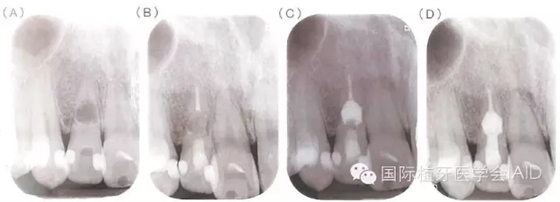

牙根內(nèi)吸收若是早期發(fā)現(xiàn),在未與牙周組織相通的情況下治療步驟相對(duì)單純以徹底去除導(dǎo)致牙髓腔內(nèi)感染與內(nèi)吸收窩洞內(nèi)的肉芽組織為首要目標(biāo),可運(yùn)用機(jī)械性的清創(chuàng)配合次氯酸鈉溶液與超聲波器械的沖洗,加強(qiáng)清創(chuàng)效果,之后于根管內(nèi)放置氫氧化鈣至少1~2周,在無(wú)臨床癥狀下,便能以古塔膠熱塑性封填系統(tǒng)(warmgutta percha technique)或是三氧礦化物(MTA,mineral trioxide aggregate)進(jìn)行根管封填;但若此內(nèi)吸收為與外界相通的牙根吸收病灶,由于MTA具有良好的密封能力(sealingability)及生物兼容性(biocompatibility)會(huì)是更恰當(dāng)?shù)倪x擇(下圖)。

(A)31歲男性因牙位12顏色改變求診,該牙無(wú)臨床癥狀,但X光檢查發(fā)現(xiàn)在牙根中段有一個(gè)約4.5*5mm的橢圓形呈放射線透性影像,檢查時(shí)牙髓組織已無(wú)活性反應(yīng)并診斷為牙根內(nèi)吸收。(B)于顯微鏡下進(jìn)行根管治療,根管內(nèi)有出血現(xiàn)象且有肉芽組織沾粘于管壁,懷疑病灶與根管外相通,移除發(fā)炎組織后進(jìn)行根管清創(chuàng)搭配超音波器械沖洗,并放置氫氧化鈣。根管封填分兩部份進(jìn)行,先以古塔膠填充填下半部根管;(C)以MTA充填于吸收窩洞,確認(rèn)MTA硬化后,以復(fù)合樹(shù)脂填補(bǔ)根管開(kāi)口;(D)根管治療完成后一年的追蹤,該牙無(wú)癥狀且周邊組織愈合良好。